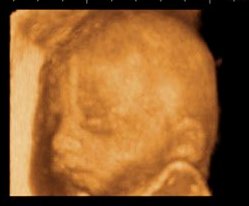

La crescita del bambino ha raggiunto la lunghezza di circa 32 cm e il peso intorno ai 700 g. Le ossa acquisiscono una consistenza più dura, mentre la pelle, ancora sottile e delicata, si copre di vernice caseosa, che la protegge dall’azione acida del liquido amniotico. Sulle sue dita, ormai complete, compaiono le unghie, le palpebre cominciano ad aprirsi e sulla lingua si sviluppano le papille gustative. È da questo momento che il piccolo comincia a sviluppare i gusti alimentari: tramite il liquido amniotico, che ingoia, assaggia i sapori dei cibi assunti dalla mamma durante la gravidanza. Ma di questo parleremo successivamente in modo più approfondito.

Il bambino ora pesa circa 850 grammi ed è lungo circa 35 centimetri. I nervi del suo sistema uditivo si sviluppano sempre di più e il liquido amniotico che lo circonda veicola i suoni che arrivano dall’esterno fino alle sue orecchie, specialmente quelli del battito del tuo cuore, dello stomaco, dell’intestino e delle voci di mamma e papà. Ora lui può ascoltare tutti questi suoni e li riconoscerà una volta nato. Le palpebre cominciano ad aprirsi, l’iride si caratterizza di quel colore blu tipico dei neonati, il grasso sottocutaneo si accumula sempre di più per la sua termoregolazione e i testicoli, nei maschietti, scendono nello scroto.

In questa settimana il bambino arriva a pesare circa 1000 grammi, con una lunghezza di circa 38 centimetri. Gioca con le manine e si succhia il dito, il cervello è sempre in costante sviluppo. I suoi polmoni hanno completato la loro formazione, con l’aiuto del liquido amniotico che il piccolo respira, ma ancora non sono in grado di funzionare. Si devono sviluppare delle cellule particolari che producono una sostanza in grado di mantenere i polmoni, e soprattutto gli alveoli, ben distesi e gonfi per permettere gli scambi gassosi. Questa sostanza si chiama surfactante e la sua formazione terminerà in linea di massima alla trentacinquesima settimana di gestazione compiuta.

Il piccolo ora arriva a pesare circa 1100 grammi ed è lungo circa 39 centimetri. La crescita in lunghezza ora comincia a diminuire, mentre accelera la crescita del peso, anche dovuta al grasso sottocutaneo che si accumula e lo fa sembrare più rotondetto. La pelle si ricopre di quella sottile peluria definita lanugo che verrà persa alla nascita e viene protetta dalla vernice caseosa. I movimenti si fanno sentire notevolmente perché lo spazio comincia a diminuire.